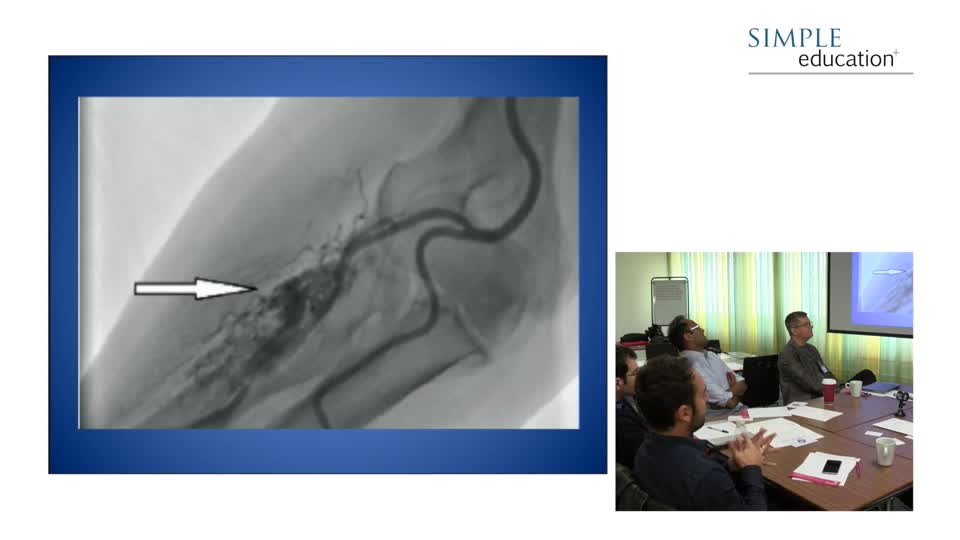

Recorded Live Case and Discussion - Dr. Justin Davies, Dr. Chris Baker and Dr. Sayan Sen